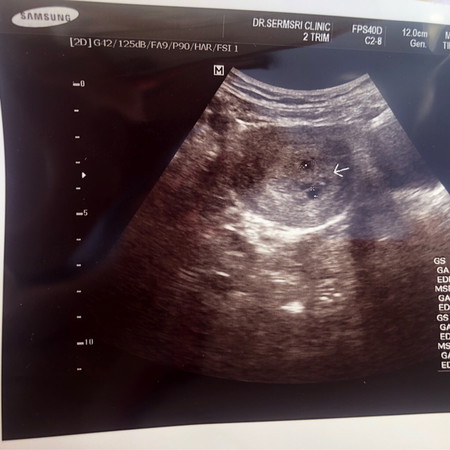

ตั้งครรภ์แล้วไปตรวจได้5 สัปดาห์ค่ะ หมอบอกว่า ถุงข้างบนคือถุงการตั้งครรภ์มีน้องอยู่ค่ะ แต่ถุงข้างล่างหมอมองเห็นเหมือนเป็นโพรงมดลูก แต่เราบอกหมอว่าเรามีกรรมพันธุ์แฝดนะค่ะจะเป็นไปได้หรือเปล่า หมดนัดตรวจอีกที 19 กุมภาพันธ์ นี้ค่ะ แม่ๆคนไหนเคยเจอเหตุการณ์แบบนี้บ้างค่ะ #ท้องแรกคะ